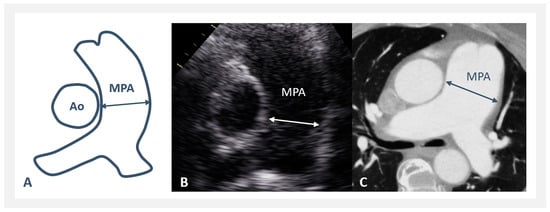

- The MPA/Ao asc diameter ratio was significantly greater in PAH-CHD (0.68–2.3, median 1.3), but not in rTOF/PR (0.46–1.52, median 0.74), compared to NORMAL (0.52–1.09, median 0.8)—Figure 2C. MPA/Ao asc ratio did not show statistically significant changes with age in all 3 patients’ groups, as shown in Figure 3C.